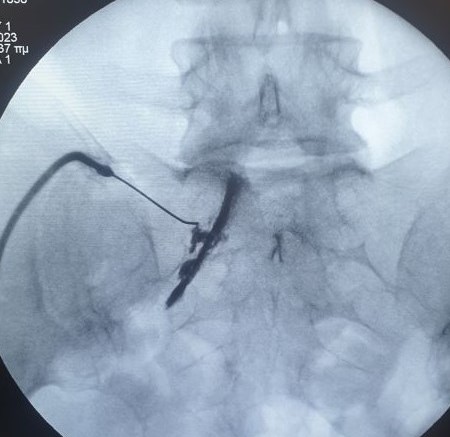

- Διατρηματική επισκληρίδιος έγχυση

- Διέγερση της ρίζας με παλμική ραδιοσυχνότητα σε περιπτώσεις μετεγχειρητικής ισχιαλγίας

- Δισκοπλαστική με χρήση laser